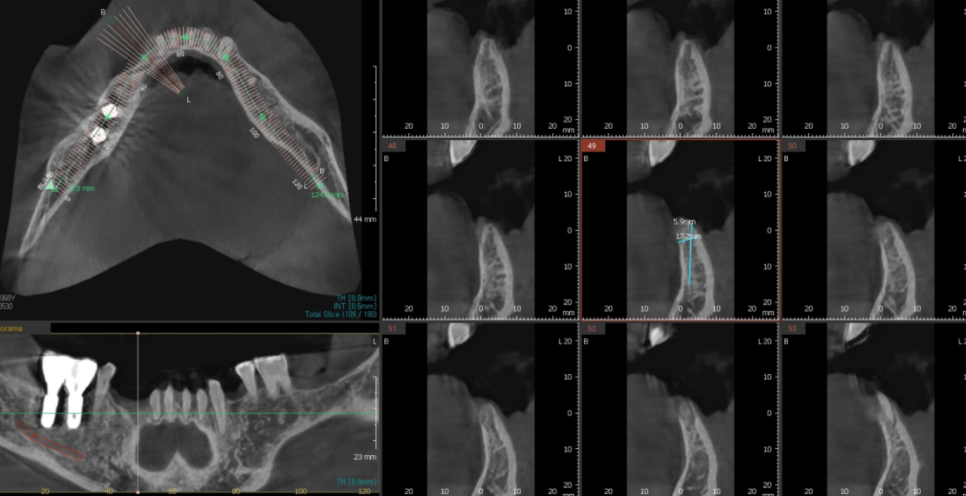

23.05.03

ct 촬영을 통해 남아있는 잇몸뼈를 분석하고

디지털 임플란트 기술로

위치, 식립 깊이, 두께 등

예측 수술도 진행했습니다.

분석된 결과물입니다.

더 이상의 실패는

환자분의 치료 의지를 꺾을 수 있기에

그 어느 때보다 철저하게 준비했던 기억이 납니다.